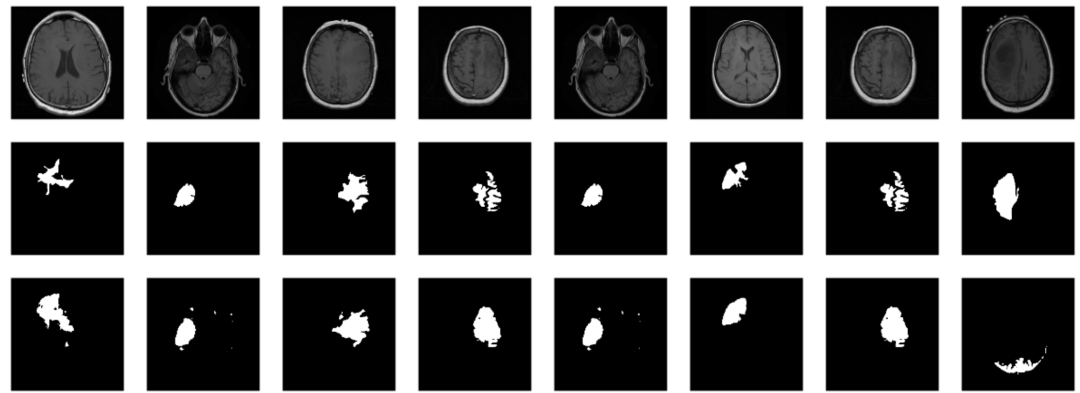

⑨ 模型评估与预测,对未知的样本预测其病变位置:

par(mfcol = c(3, 8), mar = c(0, 1, 0, 1))

cat(sprintf("\nSample %d, bce: %3f, dice: %3f\n", i, bce, dc))

inferred_mask %>% as.raster() %>% plot()